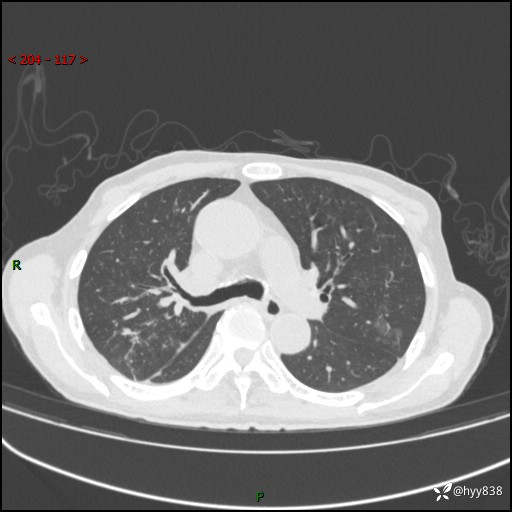

第一次胸部CT检查

现病史:患者自诉1周前无明显诱因出现咳嗽,伴咳痰,咳白色泡沫样痰,程度不剧烈,痰不易咳出,无发热、畏寒、头晕、头痛、咽痛、胸闷、胸痛、咯血、呼吸困难、四肢酸痛、腹泻、腹痛等不适,起初未予重视,未行相关诊治,1天前患者出现咳嗽,咳痰,痰中带血丝,程度不剧烈,伴食欲减退,恶心,无胸闷气促、无端坐呼吸及夜间阵发性呼吸困难,无明显呕吐,无腹痛腹泻,无血尿黑便及下肢水肿等不适,至我院急诊就诊,行胸部CT提示:右肺上叶感染并空洞形成,遂以“肺部感染”收入我科。 起病以来,患者精神、睡眠可,饮食长期欠佳,小便正常,大便便秘史约1年余,长期予灌肠排便,体力稍下降,体重无明显变化。